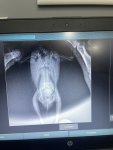

Bugün veterinere röntgen ve kontrol için tekrar götürdük ve bunlar röntgenleri.hekim bey karaciğerinde büyüme gözlemledi ve akciğerlere baskı yaptığından bu nedenle solunum sıkıntısı olduğunu söyledi.karaciğerin küçülmesi için ilaç tedavisi değil de pelet yem kullanmamızı söyledi.daha önce bu durumda olanlar varsa ya da bilgi sahibiyseniz bana yardımcı olabilir misiniz?5 gündür neftor kullanıyorduk keselim mi onu?

Karaciğer büyümesi ile ilgili zaten ilaç tedavisi değil de genelde takviyeler ile destekleme yapılır. Çok aşırı olmasa da evet var büyüme. Neftor u iki gün daha devam edip bırakabilirsiniz. Sadece pelet yem ile karaciğer küçülmez. Kaldı ki pelet yeme kuşlar alışma konusunda inatçı oluyorlar. Ben sanmıyorum pelet yemi yiyeceğini. Karaciğeri destekleyici takviyeler ile sürece devam edin.